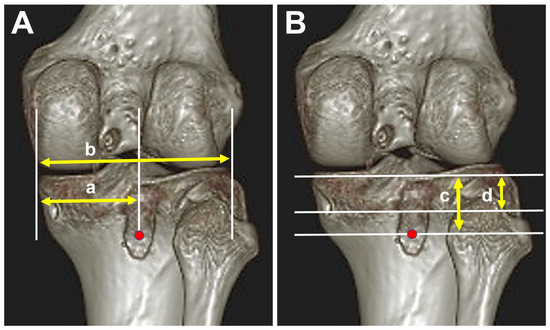

2.4. Evaluation of Tibial Tunnel Position on 3-Dimensional Computed Tomography (3D-CT)

| ML total, mm | 76.8 ± 4.1 | 76.3 ± 6.7 | 0.388 |

| ML distance, mm | 36.4 ± 7.0 | 33.9 ± 6.7 | 0.607 |

| ML percentage, % | 47.6 ± 10.0 | 44.5 ± 4.9 | 0.776 |

| PD total, mm | 22.9 ± 3.6 | 22.4 ± 2.0 | 0.768 |

| PD distance, mm | 12.5 ± 2.7 | 29.1 ± 3.5 | <0.001 * |

| PD percentage, % | 54.6 ± 6.9 | 130.6 ± 16.9 | <0.001 * |